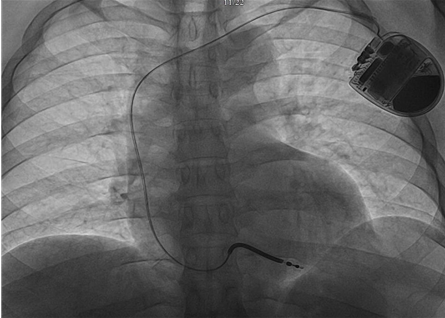

2023年5月18日,玉溪市人民医院院长、心内科专家郝应禄教授带领心内科起搏电生理团队,顺利植入玉溪首例3.0T MRI兼容植入式心律转复除颤器(ICD),该产品为全球首款3.0T & 1.5T MRI兼容ICD,也是国内首批3.0T MRI兼容ICD,消除了ICD植入后的磁共振扫描限制,为广大心律失常患者带来了3.0T全身无限制部位扫描的福音。

该患者为男性,48岁,既往诊断冠心病,陈旧性下壁、右室、正后壁心肌梗死。2023年5月7日因“突发心悸”至我院急诊科就诊,诊断为“室性心动过速”,经电复律后转律,经检查提示左室射血分数37%-42%,治疗后仍反复发作室性心动过速,诊断为:冠心病,陈旧性下壁、右室、正后壁心肌梗死,心律失常,室性心动过速,心功能II级。

患者猝死风险高,ICD指征明确,同时考虑到该名患者年轻,未来接受MRI检查诊断的需求较高,选择3.0T&1.5T MRI全身兼容单腔ICD。患者手术顺利,术后恢复良好,不仅拥有除颤器24h实时防护,也不必担心未来磁共振检查受限。